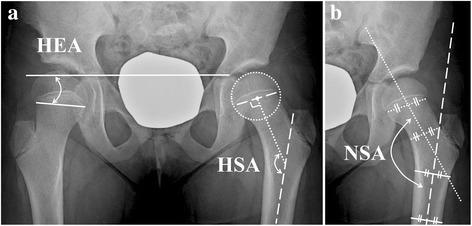

RESULTS

The mean Hilgenreiner-epiphyseal angle (HEA) of the operated side was 5.1 ± 11.3° preoperatively, and increased to 20.6 ± 11.3° at the latest follow-up (p = 0.001). The mean difference of the HEA between the operated and contralateral sides was 16.9 ± 15.1° preoperatively, which decreased to 2.4 ± 12.4° at the latest follow-up (p = 0.008). The mean articulo-trochanteric distance of the operated side, which was 3.2 ± 5.5 mm longer than that of the contralateral side preoperatively, became 5.6 ± 9.1 mm shorter at the latest follow-up (p = 0.001). The ratio of femoral neck length of the operated side to that of the contralateral side decreased over the follow-up period. Acetabular shape as measured by the Sharp angle and acetabular roof angle and femoral head coverage as measured by lateral center-edge angle did not change significantly by the index operation. The ratio of medial joint space width of the operated side to that of the contralateral side did not change significantly.

患侧术前平均希尔根赖纳骨骺角(HEA)为5.1±11.3°,最新随访时增加至20.6±11.3°(p = 0.001)。患侧与对侧HEA的术前平均差值为16.9±15.1°,最新随访时降至2.4±12.4°(p = 0.)。患侧术前关节转子间距离比对侧长3.2±5.5mm,最新随访时缩短至5.6±9.1mm(p = 0.001)。随访期间患侧股骨颈长度与对侧股骨颈长度的比值下降。通过夏普角和髋臼顶角测量的髋臼形态以及通过外侧中心边缘角测量的股骨头覆盖情况在初次手术后无明显变化。患侧与对侧内侧关节间隙宽度的比值无明显变化。